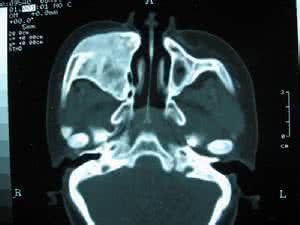

鼻窦气压伤是指外界的气压骤然变化,鼻腔内的气压跟外部气压不能平衡引起的一系列鼻窦损伤。鼻窦气压伤的高发人群是飞行员和高气压下的工作人员,比如:潜水员和隧道工作人员。由于他们的工作环境气压的变化太大所以很容易发生鼻窦气压伤。鼻窦气压伤多发生于额窦或者是上颌窦。

发生鼻窦气压伤主要表现为面额部疼痛和磨牙或者牙齿麻木,鼻内分泌物呈沾粘状,且带有血丝。严重者会出现化脓并伴随发热的症状。